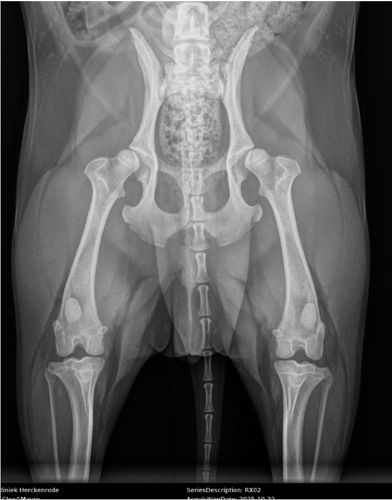

Hasselt, le 2 février 2026 – Une équipe de deux vétérinaires orthopédistes a implanté deux prothèses de hanche sur mesure imprimées en titane 3D chez un chien. Mauro, un beagle d’environ 20 kg, souffrait d’une dysplasie sévère de la hanche, une affection héréditaire qui provoque des douleurs et des difficultés locomotrices. Le succès de cette opération illustre comment l’innovation technologique et la collaboration au sein d’équipes spécialisées définissent l’avenir des soins vétérinaires.

Mauro avait des difficultés à marcher et à se lever. Il ne supportait pas les longues promenades. Fin octobre dernier, il a été examiné au AniCura Dierenartsencentrum Herckenrode à Hasselt. « Après un examen orthopédique, il est rapidement apparu que Mauro ressentait de la douleur lors de l’extension des hanches et que les articulations étaient instables », explique Tom Volkaert, vétérinaire orthopédiste chez AniCura Herckenrode. « Il s’agit de symptômes typiques de la dysplasie de la hanche, une affection héréditaire par laquelle l’articulation de la hanche ne se développe pas correctement, ce qui entraîne un mauvais ajustement de la tête fémorale dans la cavité et se traduit par des douleurs, de l’instabilité et, à terme, de l’arthrose. »

« Dans un premier temps, nous avons opté pour un traitement avec des analgésiques et du repos, car les prothèses 3D n’étaient pas encore disponibles en Belgique à l’époque », précise Tom Volkaert. « Mauro était éligible à une approche innovante avec des prothèses de hanche entièrement personnalisées et imprimées en titane 3D. » Sur la base d’un scanner CT, un implant a été conçu à l’aide d’un logiciel CAO, puis imprimé en titane couche par couche. L’implant stabilise les hanches afin d’empêcher toute luxation ultérieure. Grâce à une technique chirurgicale peu invasive, Mauro a pu marcher immédiatement après l’opération et a été autorisé à rentrer chez lui dans les 24 heures.